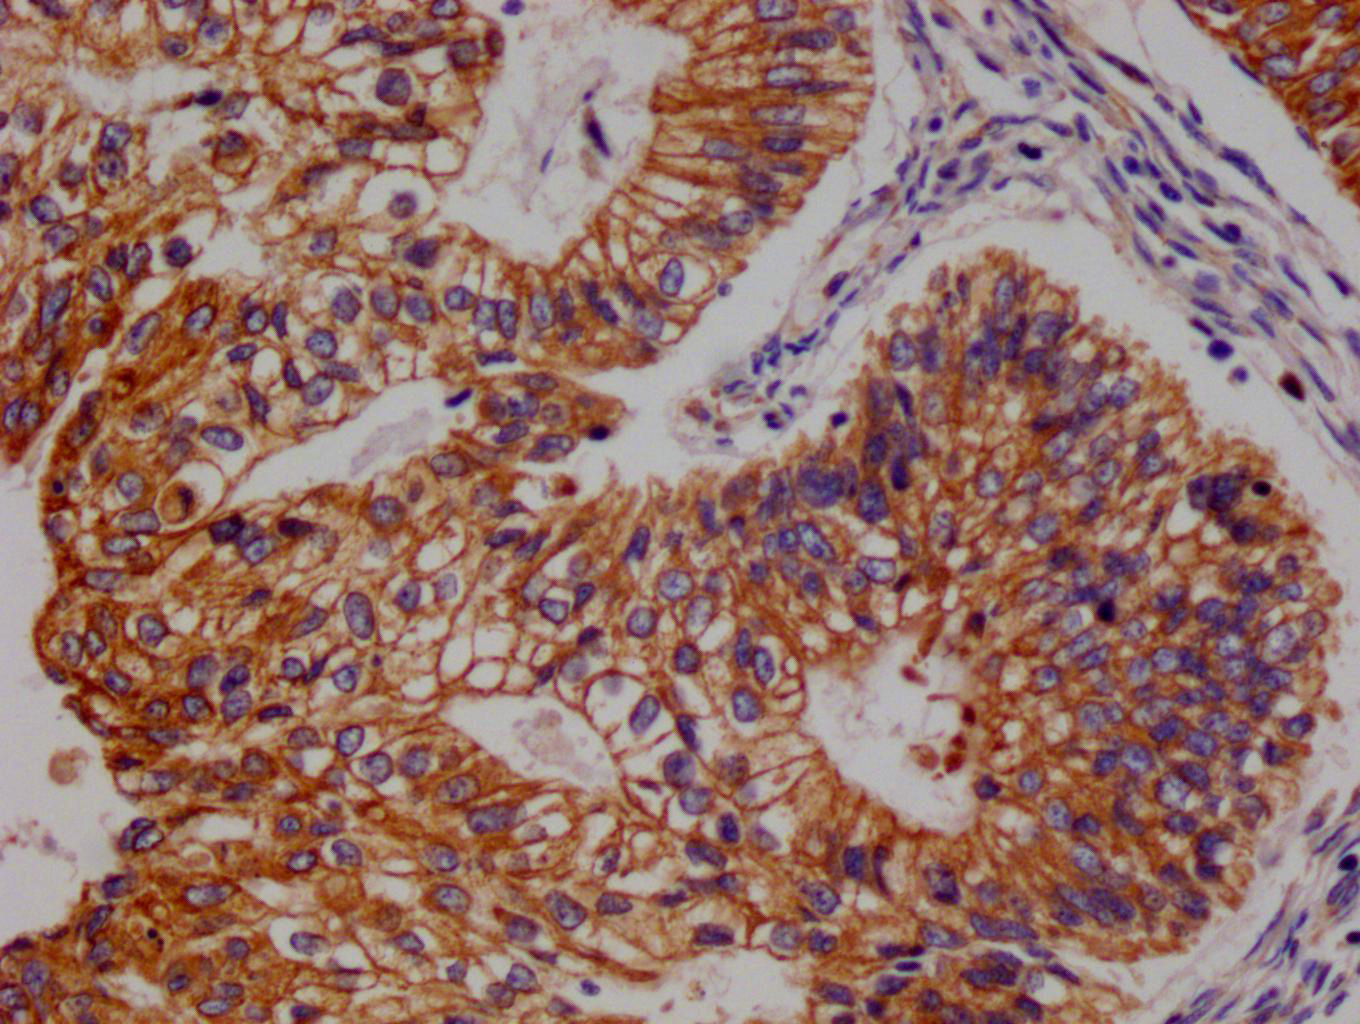

• IHC image of CSB-RA155442A0HU diluted at 1:100 and staining in paraffin-embedded human endometrial cancer performed on a Leica BondTM system. After dewaxing and hydration, antigen retrieval was mediated by high pressure in a citrate buffer (pH 6.0). Section was blocked with 10% normal goat serum 30min at RT. Then primary antibody (1% BSA) was incubated at 4°C overnight. The primary is detected by a Goat anti-rabbit polymer IgG labeled by HRP and visualized using 0.05% DAB.